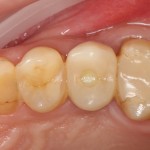

Через несколько месяцев, когда мы подойдем к финишу комплексного стоматологического лечения, мы поменяем эту коронку на постоянную, из керамики. И внешний вид, цвет и фактура будут совершенно другими. Как, например, в этом случае:

Попробуйте на этой фотографии найти коронку на импланте. Ответ — в апдейте через несколько дней.